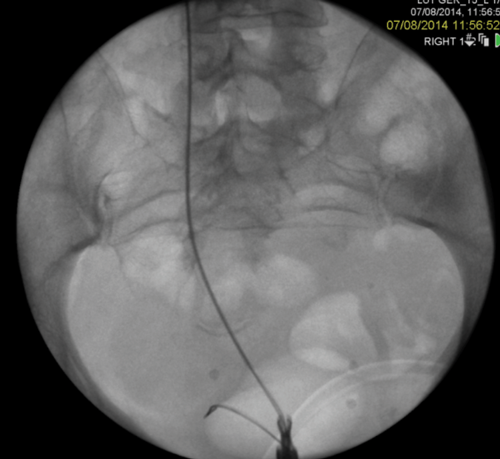

Figure 2: A Rendezvous in a patient with prostate cancer obstructing the left ureteric orifice, a partial staghorn calculus in the left kidney and left lower ureteric stones. Resection of tumour over ureteric orifice and antegrade wire.